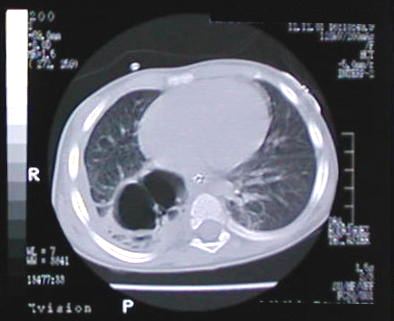

Corte Tomográfico " 2 "

Corte 2 cm por debajo al anterior:

Areas neumonicas bilaterales y el engrosamiento pleural derecho por paqui-pleuritis.

Corte Tomográfico " 3 "

Corte 4 cm. mas bajo al corte N°1:

Parenquima pulmonar del lóbulo inferior derecho cubierto de paquipleuritis

Corte Tomográfico " 4 "

Corte a nivel de base del tórax:

Parenquima pulmonar en fase neumonica observe el broncograma aereo y el proceso de paqui-pleuritis.

Corte Tomográfico " 5 "

Parenquima pulmonar de aspecto normal excepto el segmento posterobasal del lóbulo inferior derecho donde observamos cavidad bilobulada sacular de paredes engrosadas rodeado de parenquima pulmonar de aspecto neumónico.

Corte Tomográfico " 6 "

Semejante al anterior, la disminución del volumen pulmonar del hemitorax derecho.el mediastino algo desplazado a la derecha por componente neumoatelectasico pulmonar mas acentuado del lado derecho.